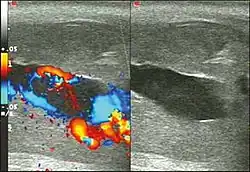

Ultrasonography

Penile ultrasonography with doppler is the imaging method of choice, because it is noninvasive, widely available, and highly sensitive. By means of this method, it is possible to diagnose priapism and differentiate between its low- and high-flow forms.[13]

In low-flow (ischemic) priapism the flow in the cavernous arteries is reduced or absent. As the condition progresses, there is an increase in echogenicity of the corpora cavernosa, attributed to tissue edema. Eventually, changes in the echotexture of the corpora cavernosa can be observed due to the fibrotic transformation generated by tissue anoxia.[13]

In high-flow priapism normal or increased, turbulent blood flow in the cavernous arteries is seen. The area surrounding the fistula presents a hypoechoic, irregular lesion in the cavernous tissue.[13]